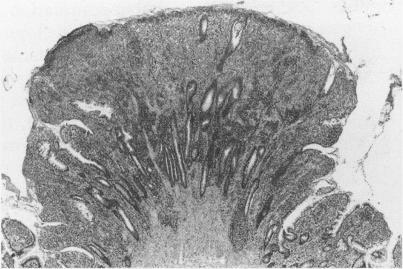

Ileostomy polyps are uncommon and poorly described. The aim of this study was to undertake a retrospective clinicopathological review of ileostomy polyps. Seven patients with 60 polyps arising on ileostomies performed for ulcerative colitis were studied. The histopathological evaluation of archival ileostomy biopsy specimens, polypectomy or excision specimens, and clinical review of patient records was undertaken. Fifty of 60 polyps were inflammatory cap polyps and six further polyps were composed of granulation tissue only. They occurred anywhere on the stoma at any time after ileostomy construction and were strongly associated with overt stomal prolapse. Four neoplastic polyps were identified in two patients 27-36 years after ileostomy construction; all occurred at the mucocutaneous junction. One patient presented with a 2 cm polypoid invasive adenocarcinoma while in the second a 1.7 cm polypoid mucinous adenocarcinoma and a 0.7 cm ileal tubular adenoma with high grade dysplasia occurred at the site of excision of a cap polyp showing focal low grade adenomatous dysplasia six years previously. Neoplastic and non-neoplastic polyps could not be differentiated clinically. It was found that most ileostomy polyps are inflammatory cap polyps associated with stomal prolapse. Less common are polypoid adenomas or adenocarcinomas arising at the mucocutaneous anastomosis > 20 years after ileostomy construction. To prevent ileostomy carcinoma it is recommended that a biopsy of all polyps at the mucocutaneous anastomosis and of any non-prolapse associated polyps elsewhere on the stoma occurring > 15 years after ileostomy construction is done.

回肠造口息肉并不常见,且相关描述较少。本研究的目的是对回肠造口息肉进行回顾性临床病理分析。我们研究了7例因溃疡性结肠炎行回肠造口术且出现60个息肉的患者。对存档的回肠造口活检标本、息肉切除术或切除标本进行了组织病理学评估,并对患者记录进行了临床回顾。60个息肉中有50个为炎性帽状息肉,另外6个息肉仅由肉芽组织构成。它们在回肠造口术后的任何时间出现在造口的任何部位,且与明显的造口脱垂密切相关。在回肠造口术后27 - 36年,在2例患者中发现了4个肿瘤性息肉;所有息肉均发生在黏膜皮肤交界处。1例患者出现了一个2 cm的息肉样浸润性腺癌,而在另1例患者中,在6年前切除的一个显示局灶性低级别腺瘤样发育异常的帽状息肉部位,出现了一个1.7 cm的息肉样黏液腺癌和一个0.7 cm的伴有高级别发育异常的回肠管状腺瘤。肿瘤性息肉和非肿瘤性息肉在临床上无法区分。研究发现,大多数回肠造口息肉是与造口脱垂相关的炎性帽状息肉。较少见的是在回肠造口术后20多年在黏膜皮肤吻合处出现的息肉样腺瘤或腺癌。为预防回肠造口癌,建议对回肠造口术后15年以上在黏膜皮肤吻合处的所有息肉以及造口其他部位任何与脱垂无关的息肉进行活检。